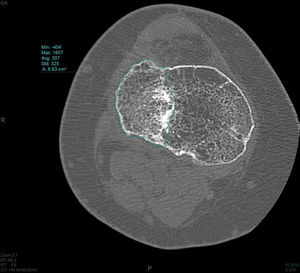

En el estudio de TC se hizo una adquisición volumétrica en un equipo multicorte a 0,6mm con posteriores reconstrucciones multiplanares de 1,5mm de espesor y 1,0mm de intervalo. En la reconstrucción en el plano coronal se analizó el punto de mayor depresión de la fractura en mm que se corresponde con el escalón articular máximo y la anchura máxima/diámetro transversal en mm; en el plano sagital se midió el diámetro máximo anteroposterior en mm del escalón articular y la caída máxima (slope) de la meseta tibial externa en grados (fig. 3). En el post-procesado en el plano axial se delimitó el contorno de la fractura y se calculó el área afecta en cm2, así como el diámetro mayor anteroposterior y la anchura máxima en mm (diámetros máximos anteroposterior y transversal) (fig. 4).